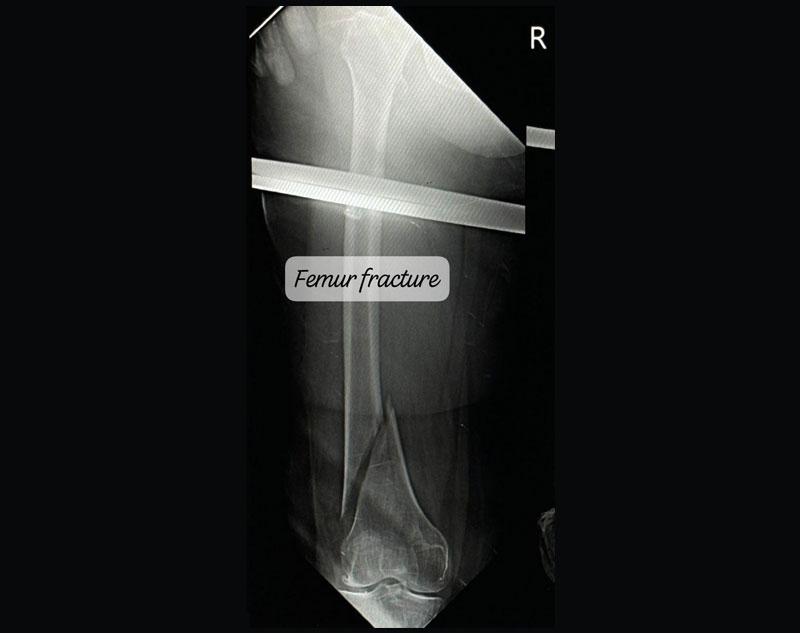

Fracture refers to the breaking or cracking of a bone. It occurs when the bone is subjected to more force than it can absorb.

There are different types of fractures, including:

Complex Trauma in orthopedics refers to severe injuries involving multiple or complicated fractures, often combined with soft tissue damage.